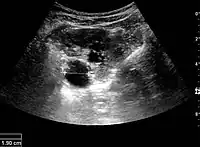

Figure 15. End-stage hydronephrosis with cortical thinning. Measurement of pelvic dilatation on the US image is illustrated by ‘+’ and a dashed line.[1]

The hydronephrosis is typically graded visually and can be divided into five categories going from a slight expansion of the renal pelvis to end-stage hydronephrosis with cortical thinning (Figure 15). The evaluation of hydronephrosis can also include measures of calyces at the level of the neck in the longitudinal scan plane, of the dilated renal pelvis in the transverse scan plane and the cortical thickness, as explained previously (Figure 16 and Figure 17).[1]